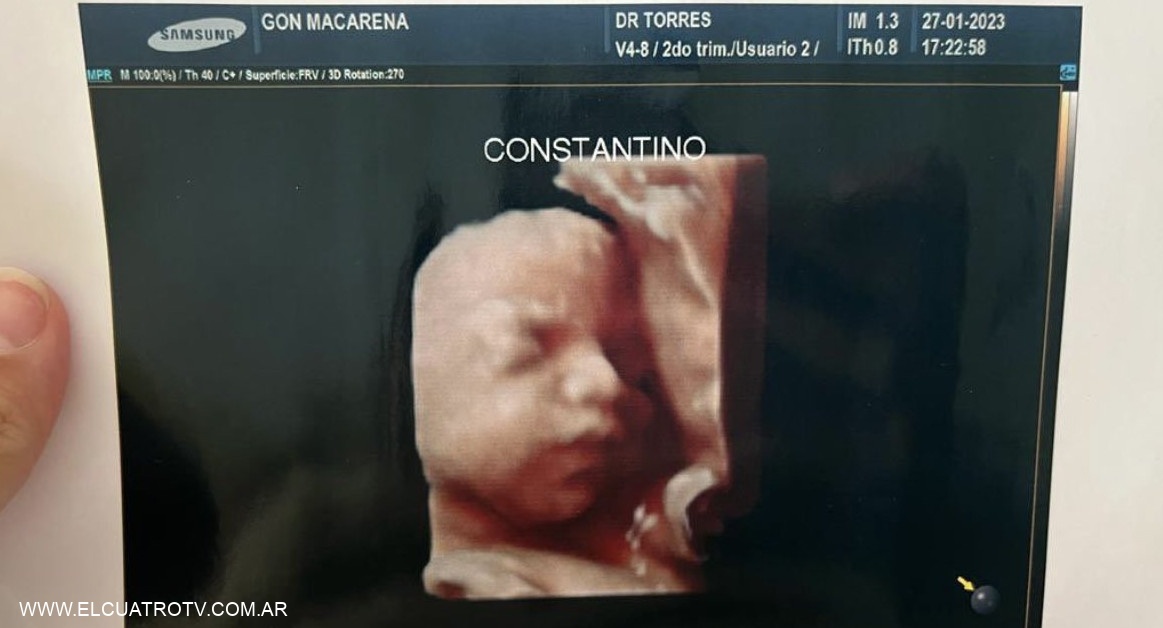

Insólita estafa: una clínica privada entregaba la misma foto de la ecografía 5D a todas sus pacientes

Insólita denuncia se realizó en Formosa. Una clínica privada fue demandada por realizar falsas ecografías 5D y entregar la misma foto a varias de sus pacientes embarazadas. El hecho se descubrió gracias a un posteo en sus redes sociales, donde dos mujeres notaron que tenían el mismo material entregado.

A través de su cuenta de Instagram, una usuaria publicó la foto del rostro de su hijo en camino. Sin embargo, apareció otra mujer para advertirle que ese no era su hijo y le mostró la imagen que creía era del bebé que ella gestaba. Allí ambas notaron que era exactamente el mismo retrato.

Denuncian a una clínica por entregar la misma foto de la ecografía 5D a todas las pacientes. Foto: Twitter.

"Ay noo, es la misma", escribió en un mensaje privado que sirvió como disparador para la denuncia contra el instituto de salud. Ambas le dijeron al medio Noticias de Formosa que asistieron al mismo lugar y hasta dieron detalles de cómo era el proceso. "Al llegar, te tomaban los datos, ingresabas a una sala donde te hacían la ecografía y luego de unos minutos la secretaria te entregaba en informe impreso”, comentaron.

Claro que el caso tomó mucha relevancia en poco tiempo, en especial en las redes sociales. A través de Twitter, una de las mujeres que fueron perjudicadas mencionó: "Por ahora somos tres mamás a las que una clínica estafó con una foto de un bebé que no es el nuestro".

"Está de más decir que encima que cobran carísimo, uno se va ilusionado por ver a su bebé y tener un lindo recuerdo. Estamos en busca de más mamás con el mismo bebé", siguió sobre el triste hecho que le tocó atravesar. Mientras se espera que en las próximas horas se haga la denuncia formal en la sede judicial, la clínica se mantiene en silencio sobre lo ocurrido.